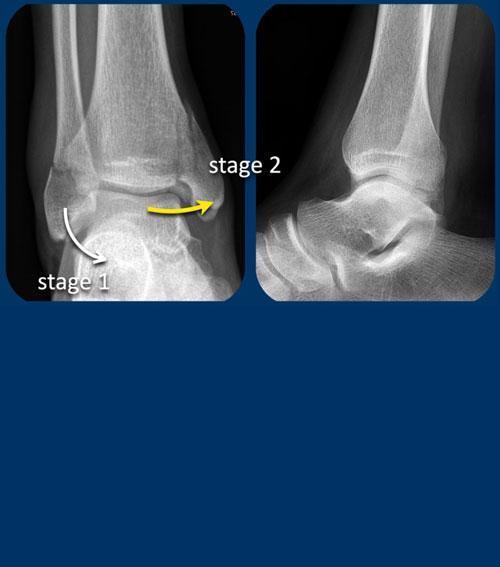

case 1 – distortion

The findings are:

- gãy xương thẳng đứng của mắt cá trong (mũi tên vàng).

Đây không phải là gãy xương do giật hay kéo, mà là gãy xương do đẩy. - Có thể có một avulsion của mắt cá ngoài (mũi tên trắng), nhưng điều đó chưa chắc chắn.

Tuy nhiên điều này không quan trọng vì chúng tôi sẽ trình bày ngay sau đây.

Gãy dọc mắt cá trong là gãy do lực đẩy.

Theo Lauge-Hansen, gãy xương xảy ra do lực khép trên bàn chân sấp.

Phía bên ngoài chịu lực căng cực độ với sự kéo giãn trên dây chằng bên ngoài.

Trong giai đoạn 1, có thể xảy ra đứt dây chằng bên ngoài hoặc gãy xương bong điểm bám (còn được gọi là Weber A).

Trong giai đoạn 2 luôn có gãy xương thẳng đứng của mắt cá trong và phải có hoặc là bong điểm bám của mắt cá ngoài hoặc đứt dây chằng bên vì các trình tự này luôn theo thứ tự này với giai đoạn 1 trước rồi đến giai đoạn 2.

Điều này có nghĩa là, dù chúng ta có thấy gãy xương ở phía bên ngoài hay không thì cũng không quan trọng.

Chắc chắn phải có tổn thương ở cả phía trong lẫn phía ngoài và chúng ta hiện biết rằng cổ chân không ổn định, vì vòng ổn định đã bị phá vỡ ở hai vị trí.

Here another unstable ankle fracture.

Theo Lauge-Hansen đây là giai đoạn SA 2.

Theo Weber đây là Weber A với gãy xương thêm ở mắt cá trong.